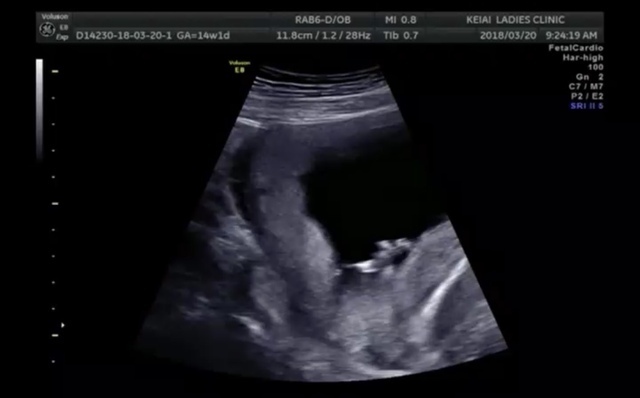

14週0日(14w0d・性別不明)|natsuki. さん(24歳)

エコー写真撮影時のエピソード:

3週間ぶりの検診で小心者の私のドキドキ、不安とは裏腹に前回の検診より成長しており一安心。初めて心音も聞かせてもらって、より一層実感が増しました。

内診中も凄い元気に飛び跳ねててかわいかったな。次の検診は4週間後なので今から楽しみ。